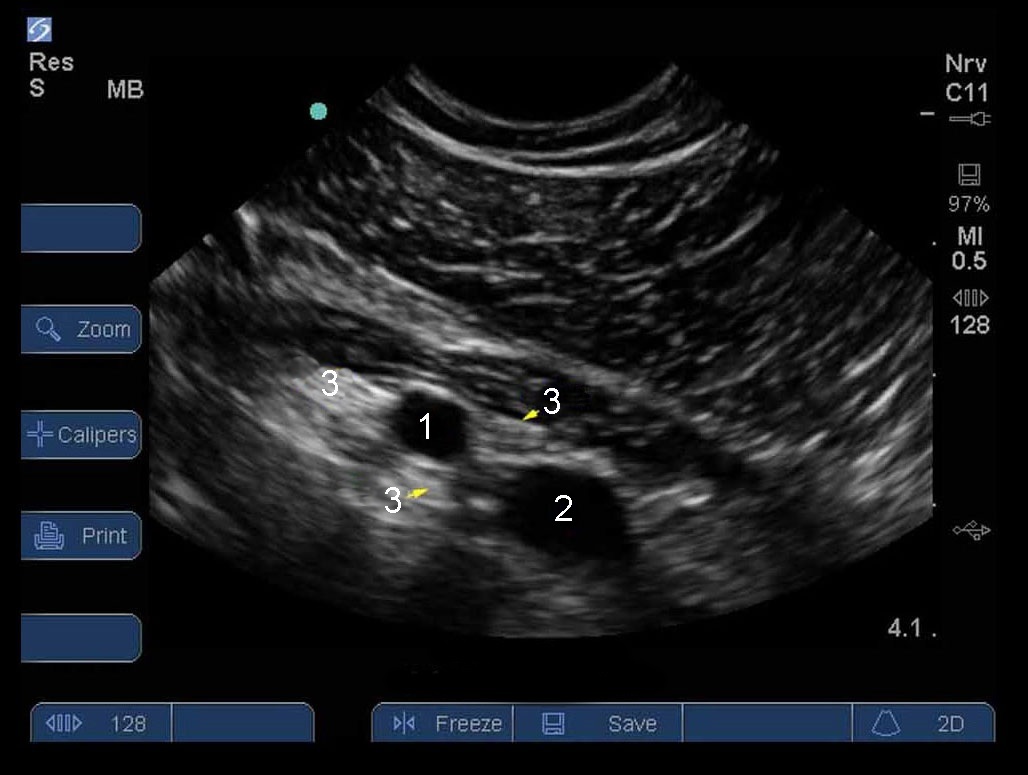

Brachial Plexus Infraclavicular Level 1

Artery

Vein

Nerves